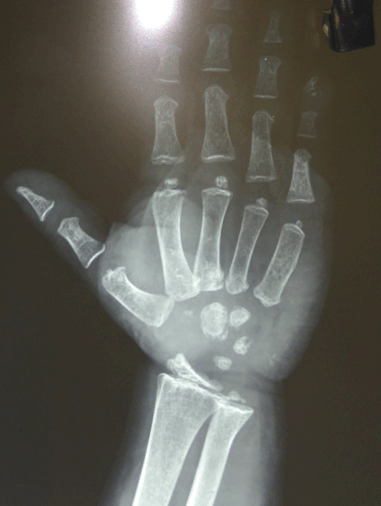

Laboratory investigations revealed normal hemogram, renal function test, hepatic function test, electrolyte, LH, FSH and prolactin. Tests also revealed very high level of TSH along with very low levels of T4 and T3. Anti-thyroid peroxidase antibody (Anti-TPO) and anti-thyroglobulin (Anti-TG) were negative in all siblings. Serum thyroglobulin was very low in all the affected siblings (Table 1). X-ray of left hand revealed significant delay in bone age and epiphyseal dysplasia (Figure 5). Ultrasonography of the thyroid gland revealed complete absence of thyroid tissue in all affected siblings. Maternal laboratory testing revealed normal anti-TPO and normally located thyroid gland on ultrasonography. Father’s thyroid function tests were normal. On Tc99m pertechnetate scan, there was no radioactive tracer uptake at any location. All the hormonal investigations were done by chemiluminescence immunoassay using Abbott ARCHITECT i1000sr immunoassay analyzer (USA).

Figure 5: X-ray left hand showing epiphysis dysplasia.